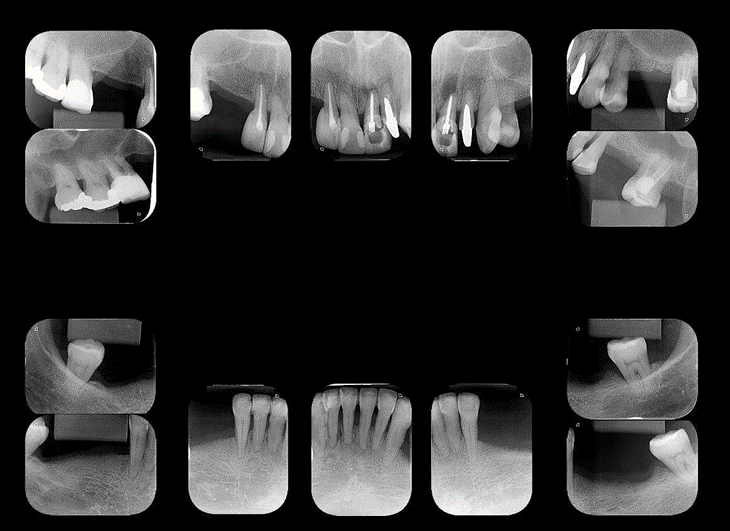

A nossa proposta é relatar o caso clínico de uma paciente de 63 anos, que procurou a faculdade em 2016 para atendimento odontológico, com queixa de mobilidade em alguns dentes, sangramento gengival e alguns espaços edêntulos. O exame radiográfico inicial indicou perda óssea generalizada, predominantemente do tipo horizontal, e alguns dentes com provável envolvimento de lesões de bifurcação (Figura 1).